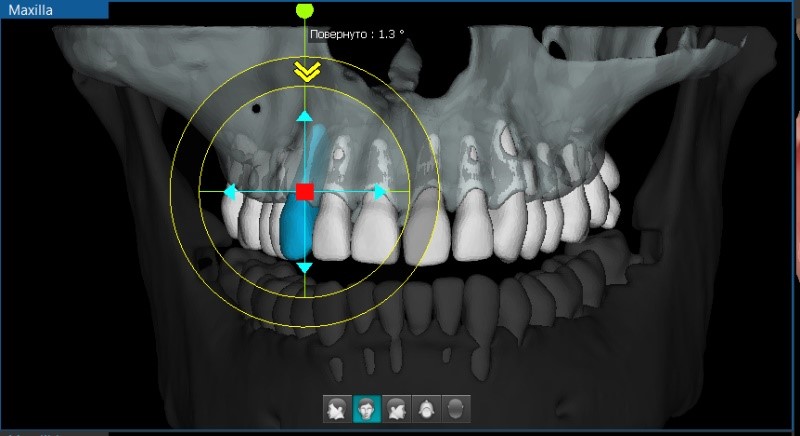

С помощью модуля Ortho выполняется моделирование процесса перемещения элементов зубочелюстной системы при помощи данных 3D-реконструкции и 3D-сегментирования костей и зубов. Каждое перемещение на виртуальной модели протоколируется и может быть сохранено как отдельное лечение.

Дистальное перемещение нижней челюсти

Перемещение отдельных зубов

Ортогнатическая хирургия

При невозможности помочь пациенту без ортогнатической хирургии, ортодонт может выбрать пути удлинения нижней челюсти с тем, чтобы нормализовать прикус и устранить диспропорцию лица. А с помощью инструмента прогнозирования мягких тканей продемонстрировать результат виртуально.

Сегментирование кости нижней челюсти вертикальным надрезом

Нормализация прикуса

Прогнозирование мягких тканей при совмещении данных 3D реконструкции и 3D-фотографии